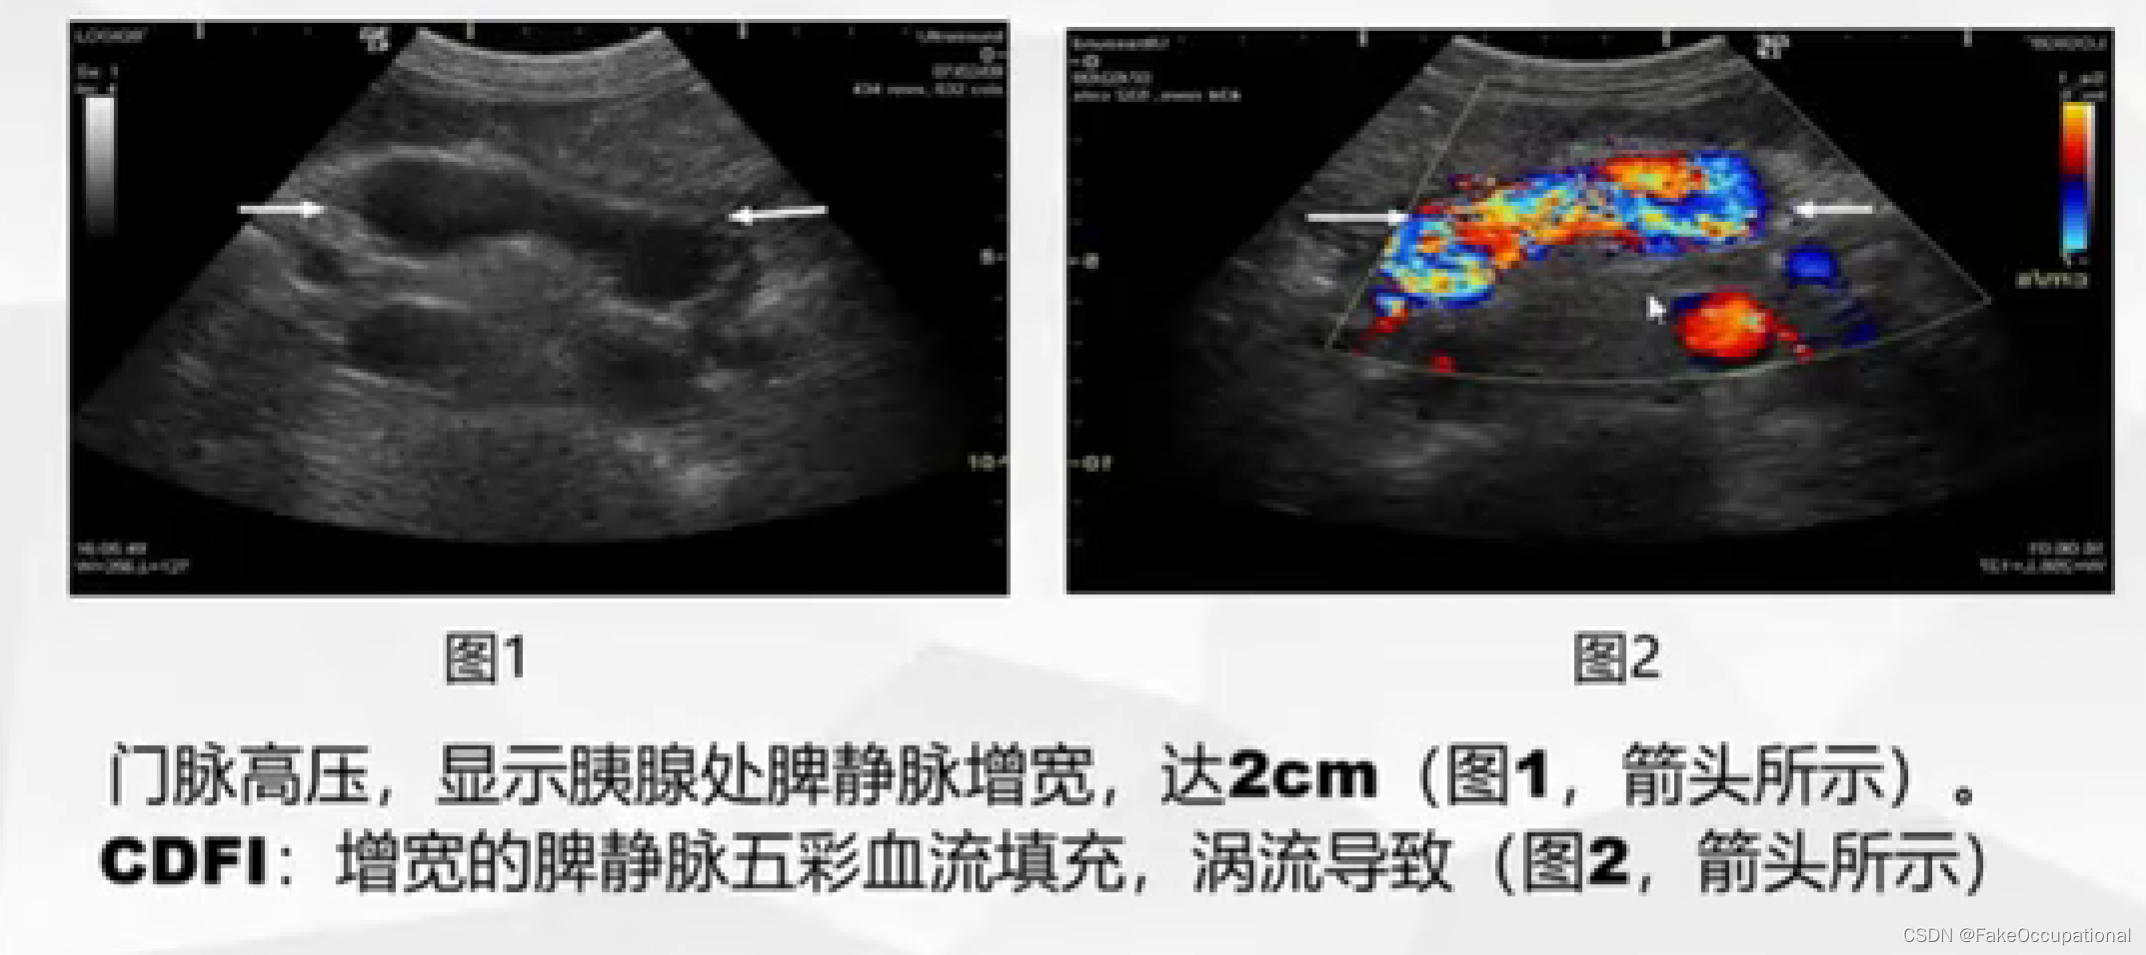

- 彩色编码实时显示血流方向、速度及血流性质:彩色多普勒血流成像(CDFI),彩色多普勒能量图(CDE)